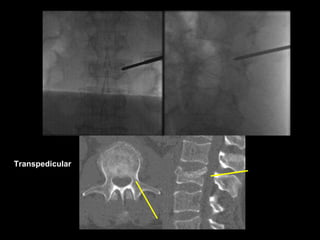

Transpedicular

Technique

After making a 1.5cm skin incision, the needle is

advanced to the facet/TP intersection